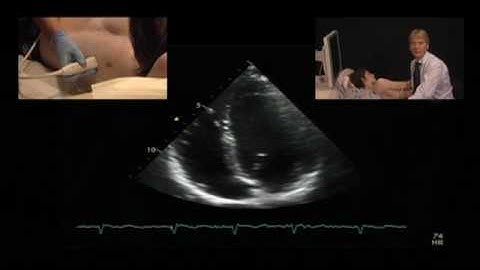

Optimizing Cardiac Views with Ultrasound